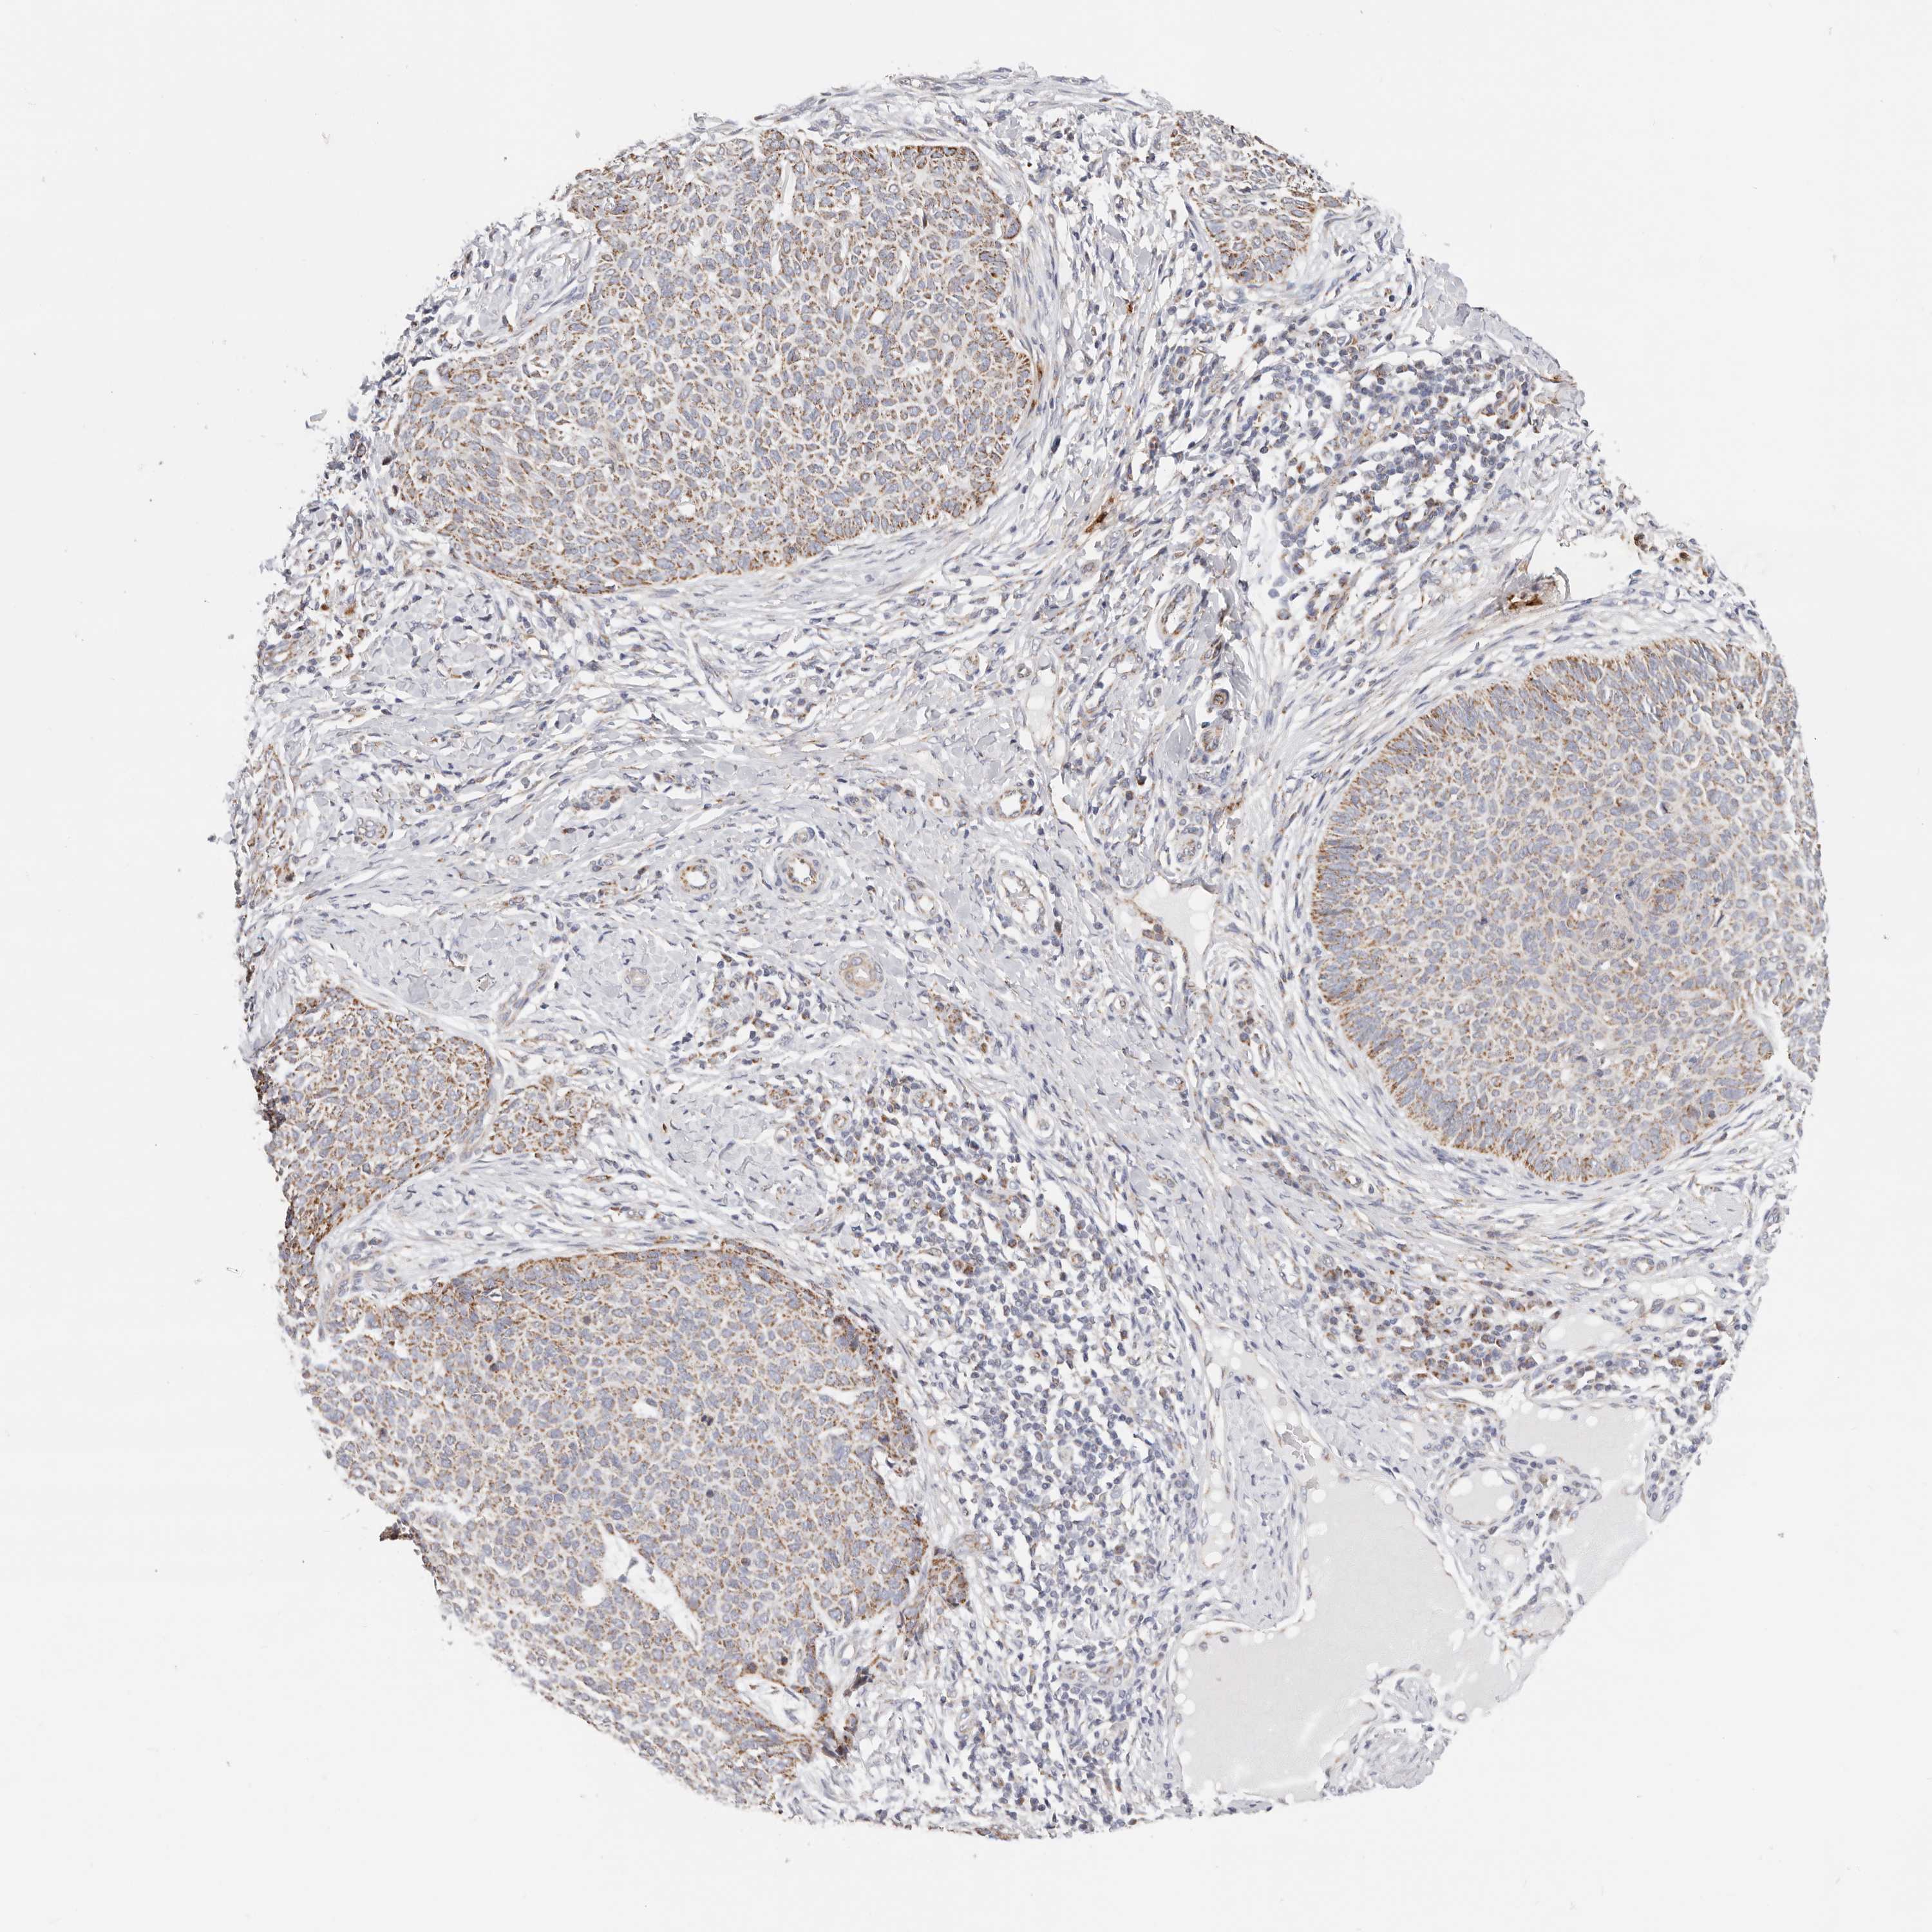

SKIN CANCER - Protein expressioni

A mouse-over function shows sample information and annotation data. Click on an image to view it in a full screen mode. Samples can be filtered based on level of antibody staining by selecting one or several of the following categories: high, medium, low and not detected. The assay and annotation is described here.

Each image is clickable and will lead to virtual microscopy that enables deeper exploration of all samples and also displays staining intensity scores, fraction scores and subcellular localization as well as patient and tissue information for each sample.

HPA030212

HPA030213

HPA030214

HPA030215

CAB013496

Basal cell carcinoma

Squamous cell carcinoma, NOS

Squamous cell carcinoma, metastatic, NOS

Adnexal tumor, benign